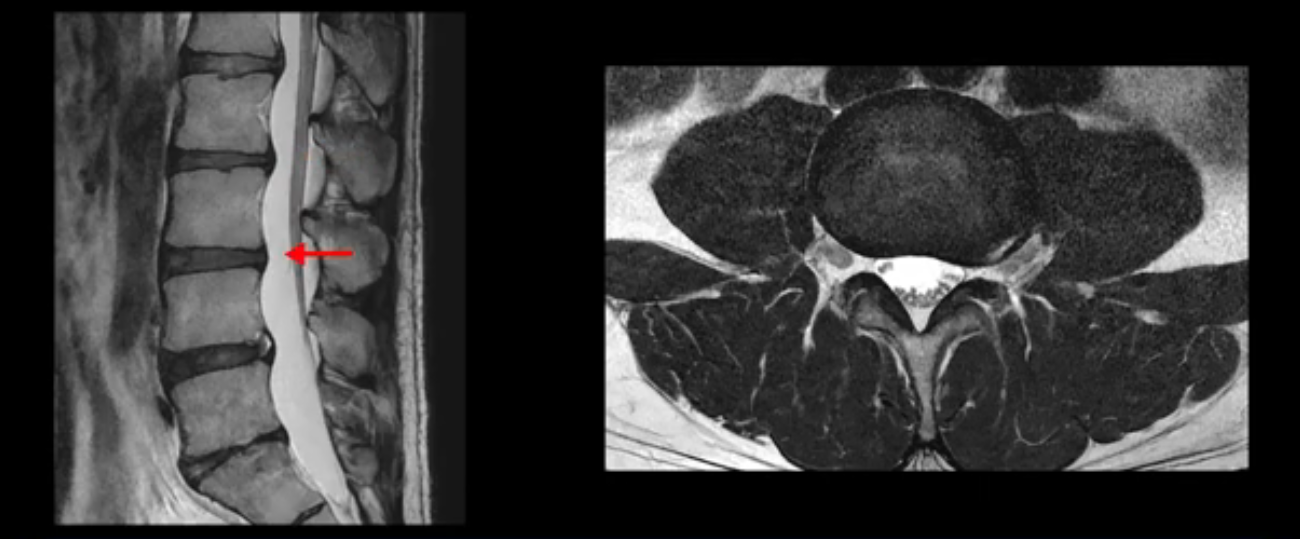

5번 1번 역시 가운데로 디스크 조금 밀려 나와있지만 신경 공간 넓이는 아주 넓어서 신경 눌림 있을 거라고 예상이 안됩니다.

추간공도 보시다시피 왼쪽, 오른쪽 전부 다 매우 넓어서 신경이 눌릴만한 부분이 전혀 보이지 않습니다.

앞서 1번 2번, 4번 5번, 5번 1번의 디스크가 찢어지고 조금 밀려 나온 게 최근에 찢어진 게 아니고 오래된 걸로 보인다고 말씀 드렸죠. 왜 그럴까요? 만약 급성으로 찢어진 것이라면 아주 심한 디스크성 통증이 있겠죠. 기침이나 재채기를 하면 심하게 아프고 허리를 조금만 구부리거나 비틀면 아주 날카로운 통증들이 생길 겁니다. 그런데 이분은 이런 증상이 전혀 아닙니다. 또 디스크의 밀려나온 정도도 전혀 심하지 않기 때문에 이분이 가지고 계신 양쪽 다리 저림, 특히 이분은 누워있을 때도 양쪽 발이 발가락까지 쑤신다고 하는데 이정도 디스크 때문에 그런 증상은 생길 수가 없는 겁니다. 이처럼 이분의 가벼운 디스크 탈출은 이미 오래 전에 진행되었고 섬유륜 자체는 이미 아문 상태인데도 디스크내장증을 진단받은 환자들 중에는 본인이 섬유륜 파열 환자라고 끝까지 믿는 분들이 많습니다. 다시 말하지만 디스크내장증이라는 진단을 받은 환자들을 보면 거의 전부 다 섬유륜 파열 증상이 아닙니다. 증상이 완전히 다릅니다. 진단이 애초에 잘못되면 어떤 치료를 받아도 좋아질 수 없습니다.